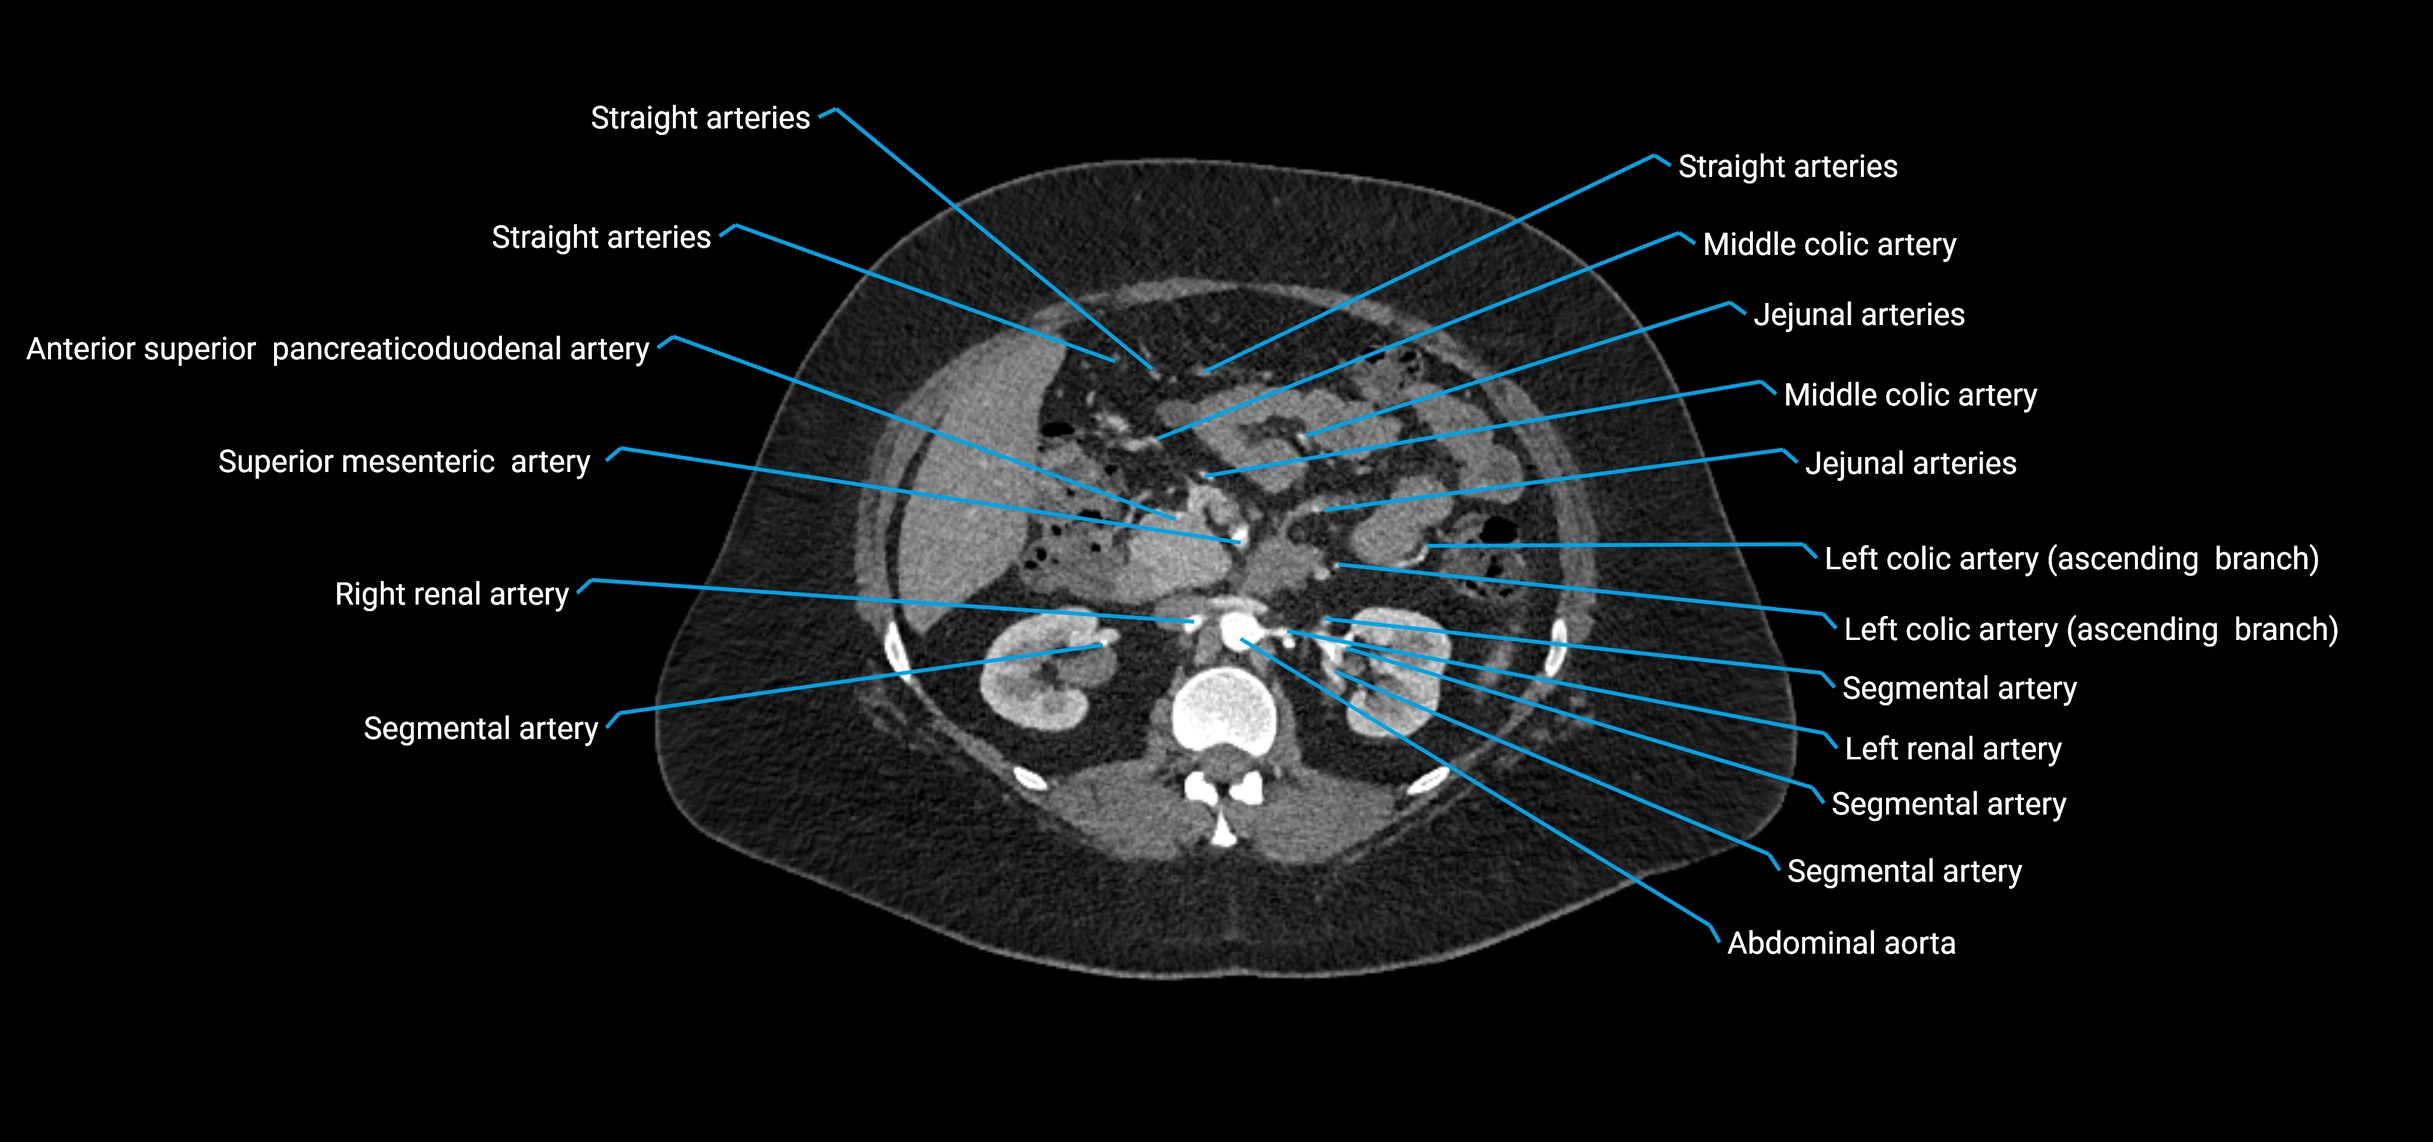

Contrast-enhanced CT (CTA):

• Gold standard for abdominal aortic imaging

• Provides excellent detail of lumen, wall, aneurysm, thrombus, and branch vessels

• Multiplanar and 3D reconstructions help in aneurysm measurement, stent graft planning, and dissection evaluation